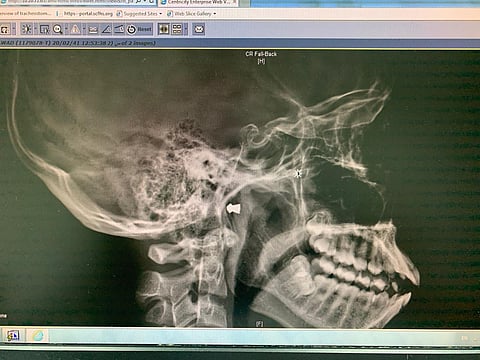

بنجاحٍ تَعامَلَ فريق طبي بقسم جراحة الأنف والأذن والحنجرة بمستشفى النور التخصصي، مع حالة شاب تَعرّض لإصابة في قاع الجمجمة من بندقية هوائية؛ حيث تَبَيّن بعد إجراء الفحوصات والأشعات اللازمة، أن الإصابة كانت بمحاذاة قاع الجمجمة، وقد تم إدخاله لغرفة العمليات تحت التخدير العام، والتعامل بنجاح مع الحالة بفضل الله، وخرج المصاب من المستشفى بعد ملاحظته وتحسّن حالته الصحية، دون أي مضاعفات ولله الحمد.